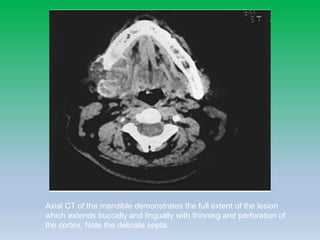

Aneurysmal bone cyst

• Rare lesions that are most common within the

mandible of children with a slight female

predominance

• Clinically these lesions present with rapid

painless facial swelling that can be disfiguring.

• The origin of ABCs is controversial: Some

investigators believe ABCs are primary congenital

lesions or vascular malformations, whereas

others believe they are acquired and arise after

local hemodynamic disturbances from trauma.

The radiograph revealed a well-defined unilocular expansile radiolucent lesion in the

posterior mandible. The lesion has caused displacement and impaction of teeth. ABC was

confirmed histopathologically.

Axial CT of the mandible demonstrates the full extent of the lesion

which extends buccally and lingually with thinning and perforation of

the cortex. Note the delicate septa.